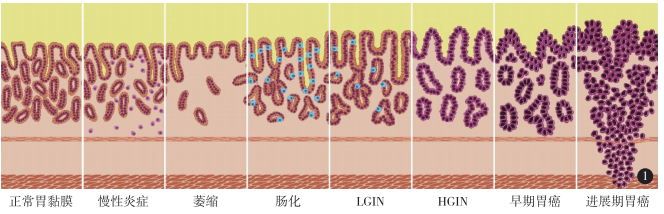

2019年,阿英腹部间断疼痛被诊断为“胃癌”,在中大五院胃肠外科行胃癌根治术,但术中医生意外发现其肝脏有微小转移灶,随即联合肝胆外科行肝脏转移瘤切除术,术后一个月检查发现,肝脏再次出现多发转移瘤。

肿瘤中心副主任曾林涓主任医师介绍,“根据病理特征,该患者的肿瘤组织免疫组化染色HER-2(+++),这意味着,她适合曲妥珠单抗靶向治疗联合化疗。在多学科讨论,全面评估患者病情后,我们制订了个体化的精准治疗方案。”

随后,阿英在医生指导下,规律地进行靶向治疗、小剂量化疗和定期营养支持治疗,至今已有20个月,远远超过晚期胃癌13个月的平均生存期,每三个月一次的复查均显示肝脏肿瘤消失,胃镜检查未见明显异常。